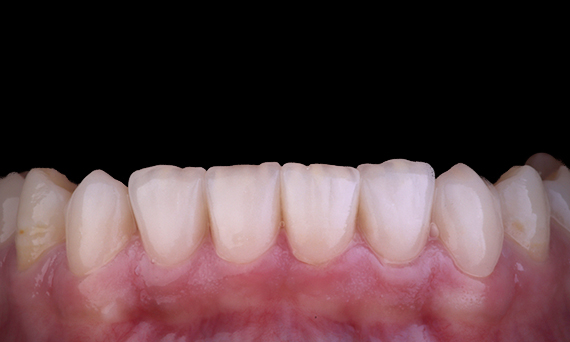

El paciente presentaba pulpitis irreversible en el diente 46. En la radiografía preoperatoria, el diente 46 se presenta con una raíz distal adicional (morfología del diente Radix Entromolaris). Los datos del CBCT confirman la presencia de raíz DL con curvatura radicular grave. Una selección cuidadosa de la lima es fundamental para esta raíz DB.

Dr. Jack Lin, endodoncista, Sídney, Nueva Gales del Sur, Australia

En esta situación, la preservación de la estructura del diente y la raíz es esencial para reducir el riesgo de desplazamiento, transporte, compresión, perforación y fractura de la raíz. La selección de casos, el diagnóstico y la planificación previa al tratamiento son muy importantes. Es fundamental la selección de limas de endodoncia con flexibilidad, eficiencia y respeto por la anatomía natural de la raíz.